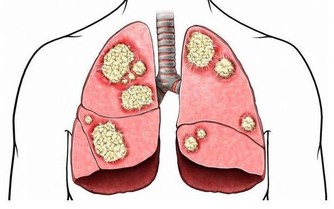

*****那麼苦瓜能不能治療癌症和糖尿病呢?*****

苦瓜是有抗癌的作用的,因為隨著研究,苦瓜的皂苷還有活性蛋白,可以很好的抑制體內癌細胞的擴散的,能夠很好的改善身體的免疫能力,苦瓜素對白血病的抑制是最明顯的,所以苦瓜是有抗癌防癌的作用的。